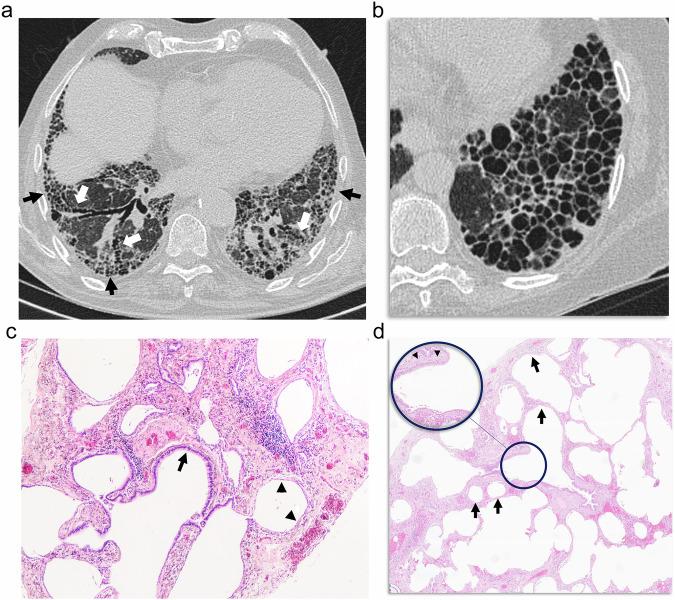

Due to destructive, fibrotic, and remodeling mechanisms, we can find a varied constellation of aerated and cystic lung lesions in smoker patients with interstitial lung disease that pose a diagnostic challenge for both radiologists and pathologists. Radiologic terminology used for cystic lung lesions in smokers is varied and sometimes confusing, and the same applies to their pathologic correlation, with different names for similar findings. Moreover, there is substantial overlap among different cystic lesions in both radiology and pathology. Ultimately, the diagnosis of a given type of cyst may lead to a wrong diagnosis with important clinical implications. In this setting, the goals of this article are to present a diagnostic approach to these lesions by correlating radiologic findings with pathology and describing a series of radiologic characteristics of these lesions, which we have called "the four S of cystic lung lesions in smokers" for size, site, shape, and surrounding of the lesions. We will define the clue radiological findings of centrilobular emphysema, paraseptal emphysema, thin-walled cysts, traction emphysema, honeycombing, smoking-related diffuse cystic lung disease, cysts in Langerhans cell histiocytosis, and cystic lesions appearing in desquamative interstitial pneumonia and we will try to show a correlation of each of these lesions with pathology for a better understanding of radiological findings. Finally, we will deal with fibrosing lung diseases and cystic lung lesions in smokers, specifically with smoking-related interstitial fibrosis and its pathological variants, and with usual interstitial pneumonia, whose prognosis is strikingly different. CRITICAL RELEVANCE STATEMENT: Knowledge of the pathological correlation of the different cystic lesions that appear in smokers with interstitial lung disease permits a better understanding of their radiological manifestations. KEY POINTS: Interstitial lung disease in smokers is characterized by varied cystic lung lesions. Cystic lesions are characterized by their size, site, shape, and surroundings. Cystic lesions in smokers may help to characterize the underlying fibrosing disease.

由于存在破坏、纤维化和重塑机制,我们在患有间质性肺病的吸烟患者中可发现多种不同类型的含气和囊性肺病变,这给放射科医生和病理科医生都带来了诊断挑战。用于描述吸烟患者囊性肺病变的放射学术语多种多样,有时令人困惑,其病理相关性也是如此,相似的表现有不同的名称。此外,不同的囊性病变在放射学和病理学上都有大量重叠。最终,对某一特定类型囊肿的诊断可能会导致错误诊断,产生重要的临床影响。在此背景下,本文的目的是通过将放射学表现与病理学相关联,提出针对这些病变的诊断方法,并描述这些病变的一系列放射学特征,我们将其称为“吸烟患者囊性肺病变的四个S”,即病变的大小、位置、形态和周围情况。我们将定义小叶中心型肺气肿、间隔旁肺气肿、薄壁囊肿、牵拉性肺气肿、蜂窝肺、吸烟相关弥漫性囊性肺疾病、朗格汉斯细胞组织细胞增多症中的囊肿以及脱屑性间质性肺炎中出现的囊性病变的关键放射学表现,并试图展示这些病变与病理学的相关性,以便更好地理解放射学表现。最后,我们将探讨吸烟患者的纤维化性肺病和囊性肺病变,特别是与吸烟相关的间质性纤维化及其病理变体,以及预后截然不同的普通间质性肺炎。关键相关性声明:了解吸烟合并间质性肺病患者出现的不同囊性病变的病理相关性有助于更好地理解其放射学表现。关键点:吸烟患者的间质性肺病以多种囊性肺病变为特征。囊性病变以其大小、位置、形态和周围情况为特征。吸烟患者的囊性病变可能有助于明确潜在的纤维化疾病。